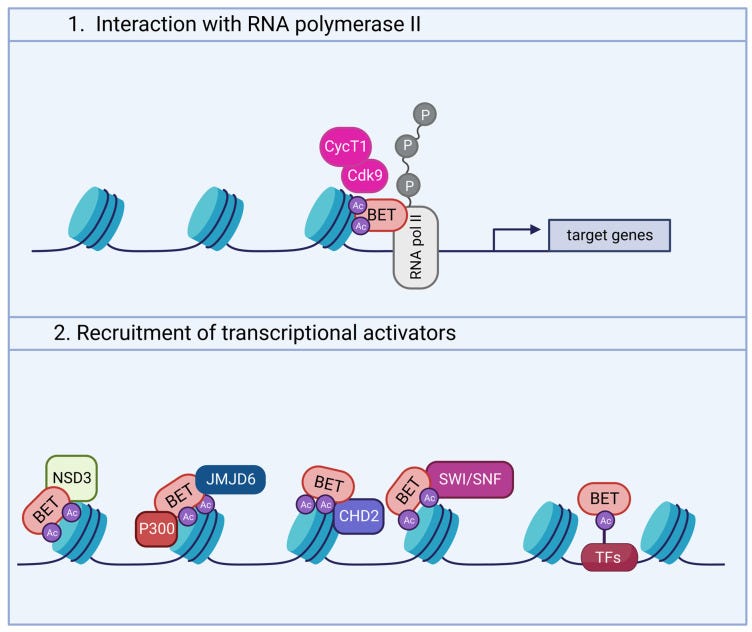

BET proteins can contribute to neuroinflammation, as per Martella et al (2023)19.

BET proteins: Bromodomain and extra-terminal proteins.

In recent years, thanks to the development of BET inhibitors, interest in this protein family has risen for its relevance in brain development and function. For example, experimental evidence has shown that BET modulation affects neuronal activity and the expression of genes involved in learning and memory. In addition, BET inhibition strongly suppresses molecular pathways related to neuroinflammation. These observations suggest that BET modulation may play a critical role in the onset and during the development of diverse neurodegenerative and neuropsychiatric disorders, such as Alzheimer’s disease, fragile X syndrome, and Rett syndrome.

Though incomplete, some evidence has shed new light into the molecular pathways linking BRD4 and neuronal activity (Figure 2). Indeed, neurotransmitter and neurotrophic factors induce signaling cascades leading to the activation of PKA and Casein Kinase 2 (CK2). These kinases, in turn, phosphorylate BRD4, favoring its binding to acetylated histones [15,45,66].

Again, disruption of BET proteins up or down may induce all manner of pathologies, the authors note that this work deserves further investigation:

Another study documented elevated abundance of Brd4 mRNA in rat striatal neurons, where BRD4 is involved in dopamine-induced and cAMP/PKA-dependent basal transcription. Indeed, cAMP/PKA signaling elicits BRD4 recruitment to genes induced by dopamine stimulation, whereas pharmacological or genetic inactivation of BRD4 significantly downregulates the transcription of a subset of genes mediated by D1R [66]. Consistent with the role of BRD4 in dopaminergic signaling, Brd4 transcript levels are much higher than Brd2 and Brd3 in nucleus accumbens (NAc), a region enriched in D1R- and D2R-expressing neurons implicated in reward mechanisms [67]. This finding is further supported by the reportedly high concentration of BET proteins in the amygdala and midbrain, also involved in reward behavior in both rodents and non-human primates [52]. Other remarkable differences in the expression of specific BETs have been detected in some neuronal subtypes. For instance, Brd2 expression is prevalent in cerebellar neurons, while the highest Brd4 levels were found in claustral neurons of the frontal cortex and in some hippocampal neurons [65].